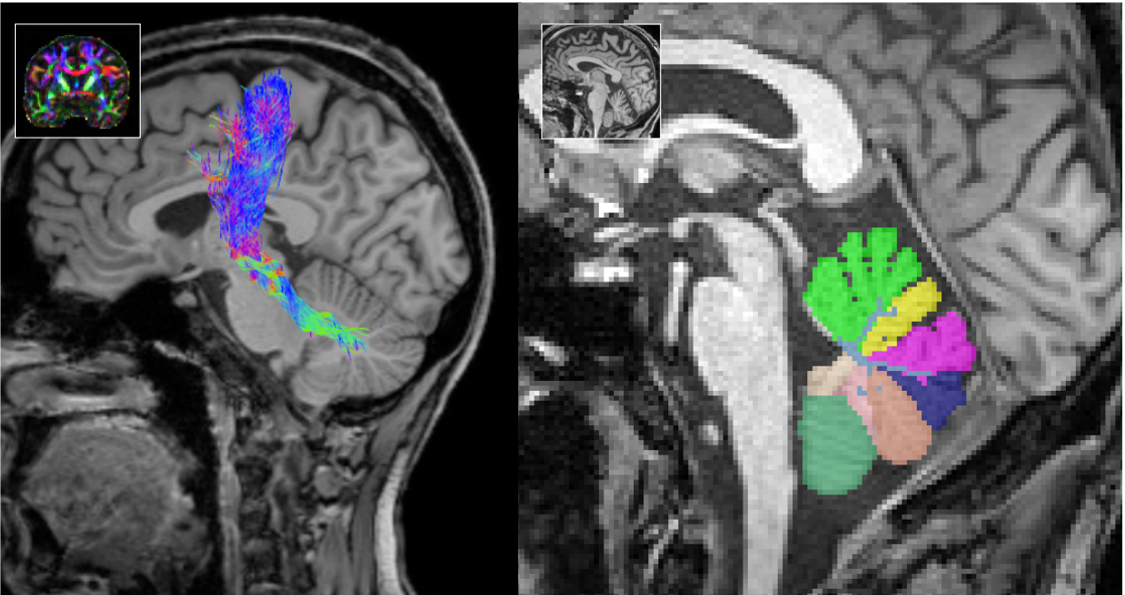

Ultra-high magnetic fields (UHF) offer significantly higher resolutions and advanced MR applications, such as iron-sensitive sequences and metabolic imaging. Thus, UHF-MR has an enormous potential to detect and monitor structural and chemical alterations at a. level of detail that cannot be achieved with a conventional fieldstrength of 3T. However, these clear advantages are opposed by technical shortcommings of field inhomogeneities, which fundamentally degrade image quality, particularly at the excentric infratentorial regions of the field of view. In collaboration with the MR Physics group at the DZNE, lead by Tony Stöcker, we have successfully implemented a comprehensive protocol including structural and metabolic sequences (T1w, T2w, FLAIR, MPM, QSM, CEST) using parallel transmission technologies (pTx) that allows imaging of the entire brain including brainstem and cerebellum in consistently high resolution without artifacts at a fieldstrength of 7T. The acquisition in patients suffering from movement disorders is currently ongoing. We hypothesize, that the increased sensitivity of UHF-MRI has the potential to substantially improve the understanding of structural and metabolic brain alterations in neurodegenerative diseases.

Automated Segmentations & AI-driven MRI Analysis

Leveraging cutting-edge artificial intelligence (AI) methods, we analyze MRI images to identify disease specific alterations. We have successfully implemented CerebNet, a fast and reliable deep-learning pipeline for detailed cerebellum sub-segmentation with high anatomical accuracy (Code on Github). Further development of CerebNet is underway, with extensions for sub-segmentation of high-resolution MRI and inclusion of the brainstem and cerebellar peduncles. Moreover, we are implementing segment anything pipelines as well as unsupervised surface analyses. Our objective is to enhance our understanding of disease related structural changes. By discerning subtle changes in the brain, we aim to contribute valuable insights that may not only deepen our comprehension of the disease but also foster the development of novel treatments by informing the design of clinical trials.